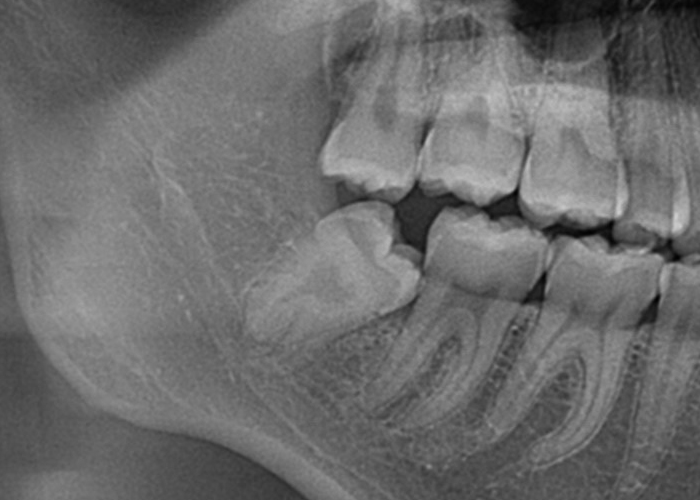

親知らずの生え方

半埋伏智歯(部分的に露出している)

半埋伏とは、親知らずの一部が歯肉の下に埋まっており、一部が口腔内に露出している状態を指します。

露出している部分には、歯垢や食物がたまりやすくなり、炎症や感染、虫歯のリスクが高まる場合があります。

また、半埋伏の親知らずは、周囲の歯や歯肉に圧迫を与え、痛みや不快感を引き起こすこともあります。

さらに、半埋伏の親知らずが隣接する歯に対して圧力をかけることで、歯列の乱れや移動が起こる場合もあります。